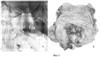

Тонус анального сфинктера сохранен. Сразу за сфинктером в 1,5-2 см от анального отверстия определяется край опухоли с преимущественным экзофитным ростом. По окружности опухоль занимает от ½ до , по длиннику до 5-6 см (фиг.1). Для объективизации распространения опухоли за пределы ее макроскопических границ выполнена прямая хромоскопия с метиленовым синим (фиг.2). Используя отличительные особенности рельефа слизистой ампулы кишки и опухоли, произведена биопсия: 1 фл. – 4 фр. с проксимального края опухоли, 2 фл. – 3 фр. из зоны диффузного пропитывания слизистой красителем, 3 фл. – 3 фр., из центральной части опухоли, 4 фл. – 3 фр. из дистального края. Толстая кишка осмотрена до купола слепой кишки. В левой половине ободочной кишки определяется несколько дивертикулов 0,8 см без признаков воспаления. Слизистая дистального отдела отечна, гиперемирована. В сигмовидной кишке полип на широком основании 0,8 см, биопсия 2 фр. Заключение: рак прямой кишки, полип сигмовидной кишки 2 типа, одиночные дивертикулы ободочной кишки.

Фиг.2 – хромоколоноскопия: А – патологический рельеф нижнего края опухоли (белая пунктирная линия) на фоне анального канала (указан черными стрелками); Б – типичный рельеф слизистой ампулы прямой кишки.